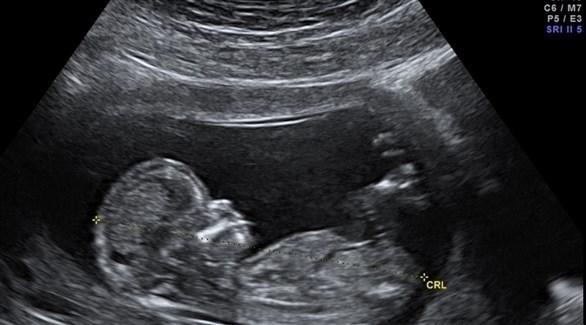

خبرني - أجرى باحثون من جامعة إدنبرة البريطانية مراجعة لدراسات عديدة سابقة أجريت عن آثار العملية القيصرية على الأم والطفل، للوقوف على مدى فوائد وأضرار هذه الطريقة على المدى الطويل. وكشفت النتائج عن تزايد إقبال النساء على الولادة القيصرية بشكل كبير، في الوقت الذي تبين فيه أن العملية القيصرية تضعف عضلات الحوض لدى الأم، وتزيد احتمالات إصابة الأطفال بالربو والبدانة في سن الطفولة.